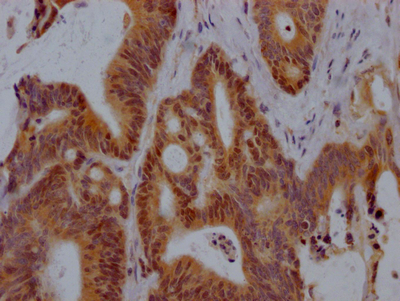

IHC image of CSB-PA666060LA01HU diluted at 1:100 and staining in paraffin-embedded human cervical cancer performed on a Leica BondTM system. After dewaxing and hydration, antigen retrieval was mediated by high pressure in a citrate buffer (pH 6.0). Section was blocked with 10% normal goat serum 30min at RT. Then primary antibody (1% BSA) was incubated at 4°C overnight. The primary is detected by a biotinylated secondary antibody and visualized using an HRP conjugated SP system.